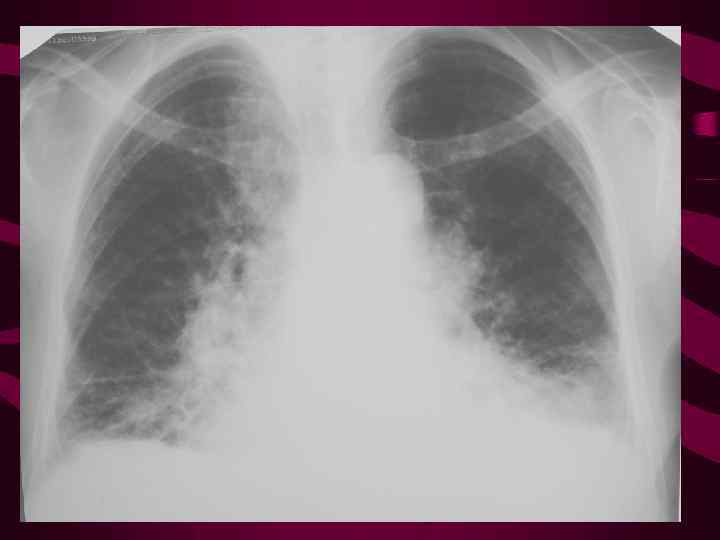

Legochnyj Risunok Usilenie Sgushenie Deformaciya Obednenie Rentgen Legkih Patologiya Odnostoronnee Usilenie Narusheniya Krovoobrasheniya Limfogennyj Karcinomatoz Pnevmoskleroz Pnevmoniya Infekciya